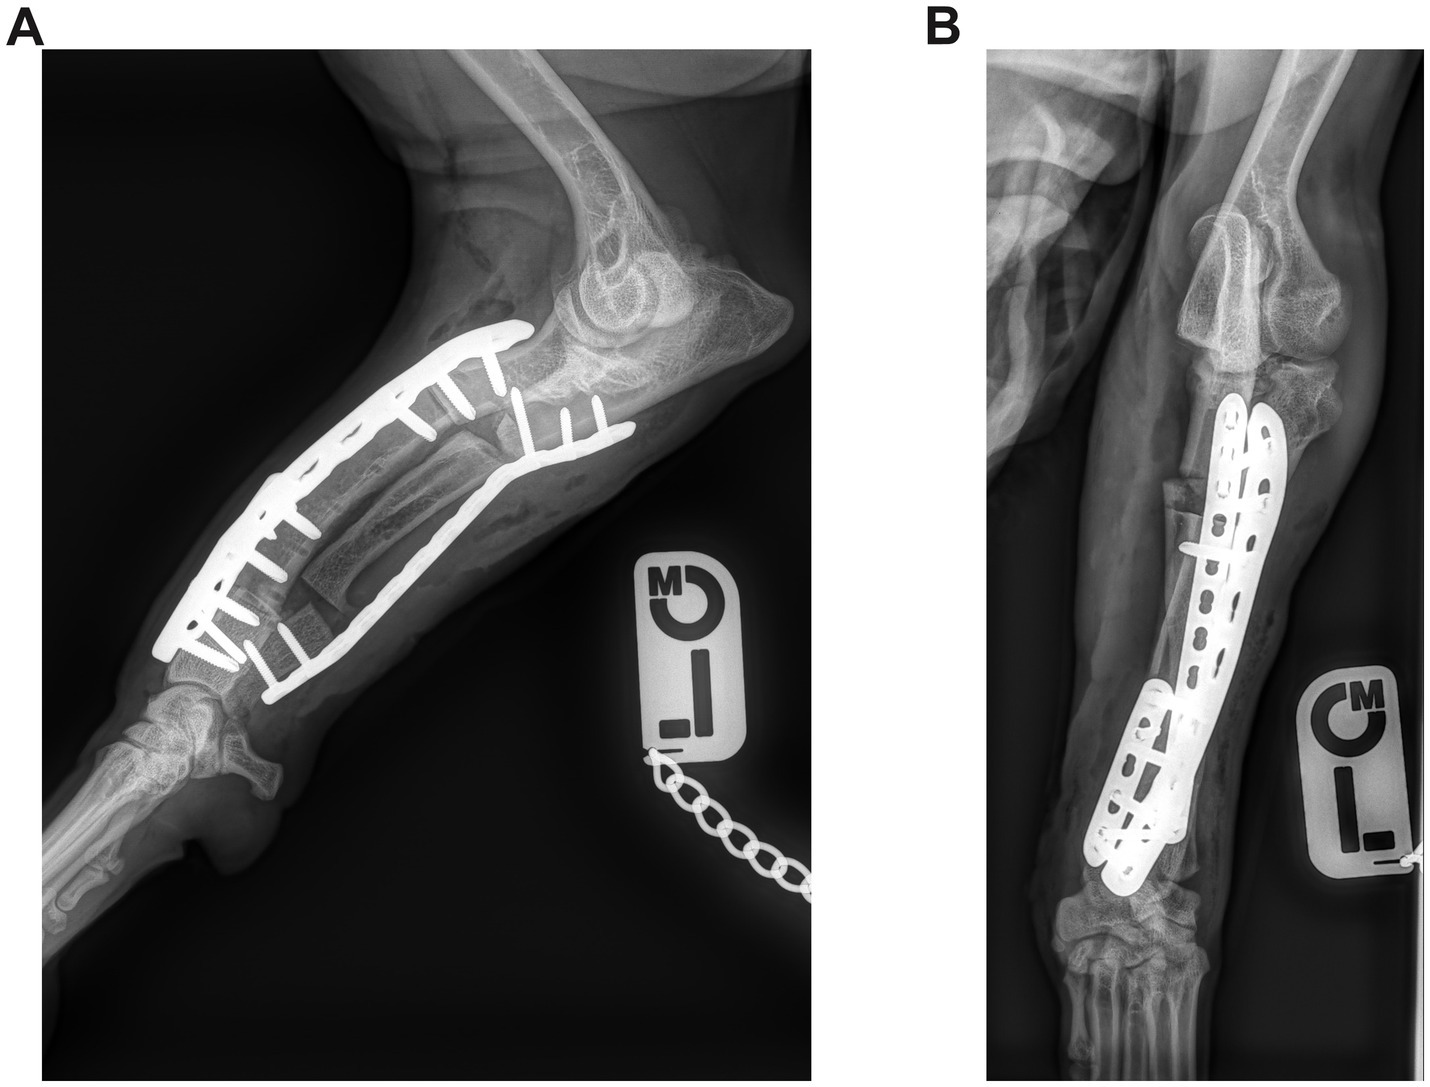

Immediately after surgery, the axial and rotational alignment of the antebrachium was grossly inspected, and orthogonal radiographs were performed to assess the adjacent joints’ orientation and implant position (Figures 3, 4). No objective measurements of antebrachial alignment were recorded. A light bandage was applied to the limb just distal to the elbow to control soft tissue swelling for 24 h. All patients were hospitalized for at least 24 h and received methadone analgesia based on the Short Form of the Glasgow Composite Measure Pain Scale (0.1–0.2 mg/kg every 2–4 h if the score was 6/24 or above).

Figure 4. (A) Postoperative mediolateral and (B) craniocaudal radiographs of the antebrachium of the dog from Figure 2. The radial ostectomies have been fixed with two Locking Compression Plates (LCP), and the ulnar osteotomies have been fixed with a single LCP.